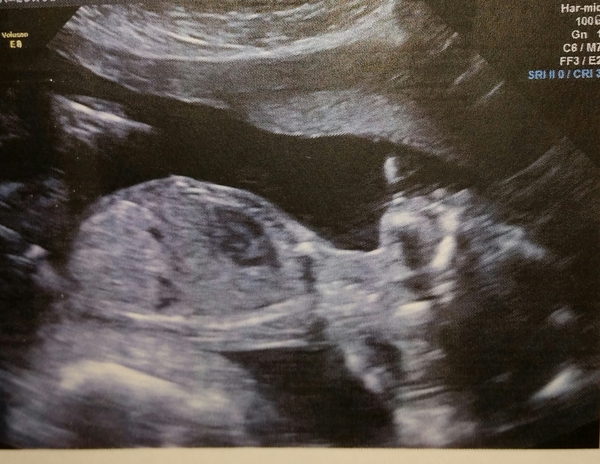

Ok, scanxiety over. All is well! Dates, measurements, everything, all good. I'm so relieved. Grin

Great Stinkersmum! Look at that! Great to hear all's well.

Congrats stinkers! We had our scan today too and bump is a wee girl! Taking time to get my head around it as I was absolutely convinced it was a boy! Delighted though!

Congrats Stinkers and Ca55! I'm also so relieved scan went well yesterday. She was so active and was so hard to get face view almost gave. I guess it's time to relax and enjoy the pregnancy??